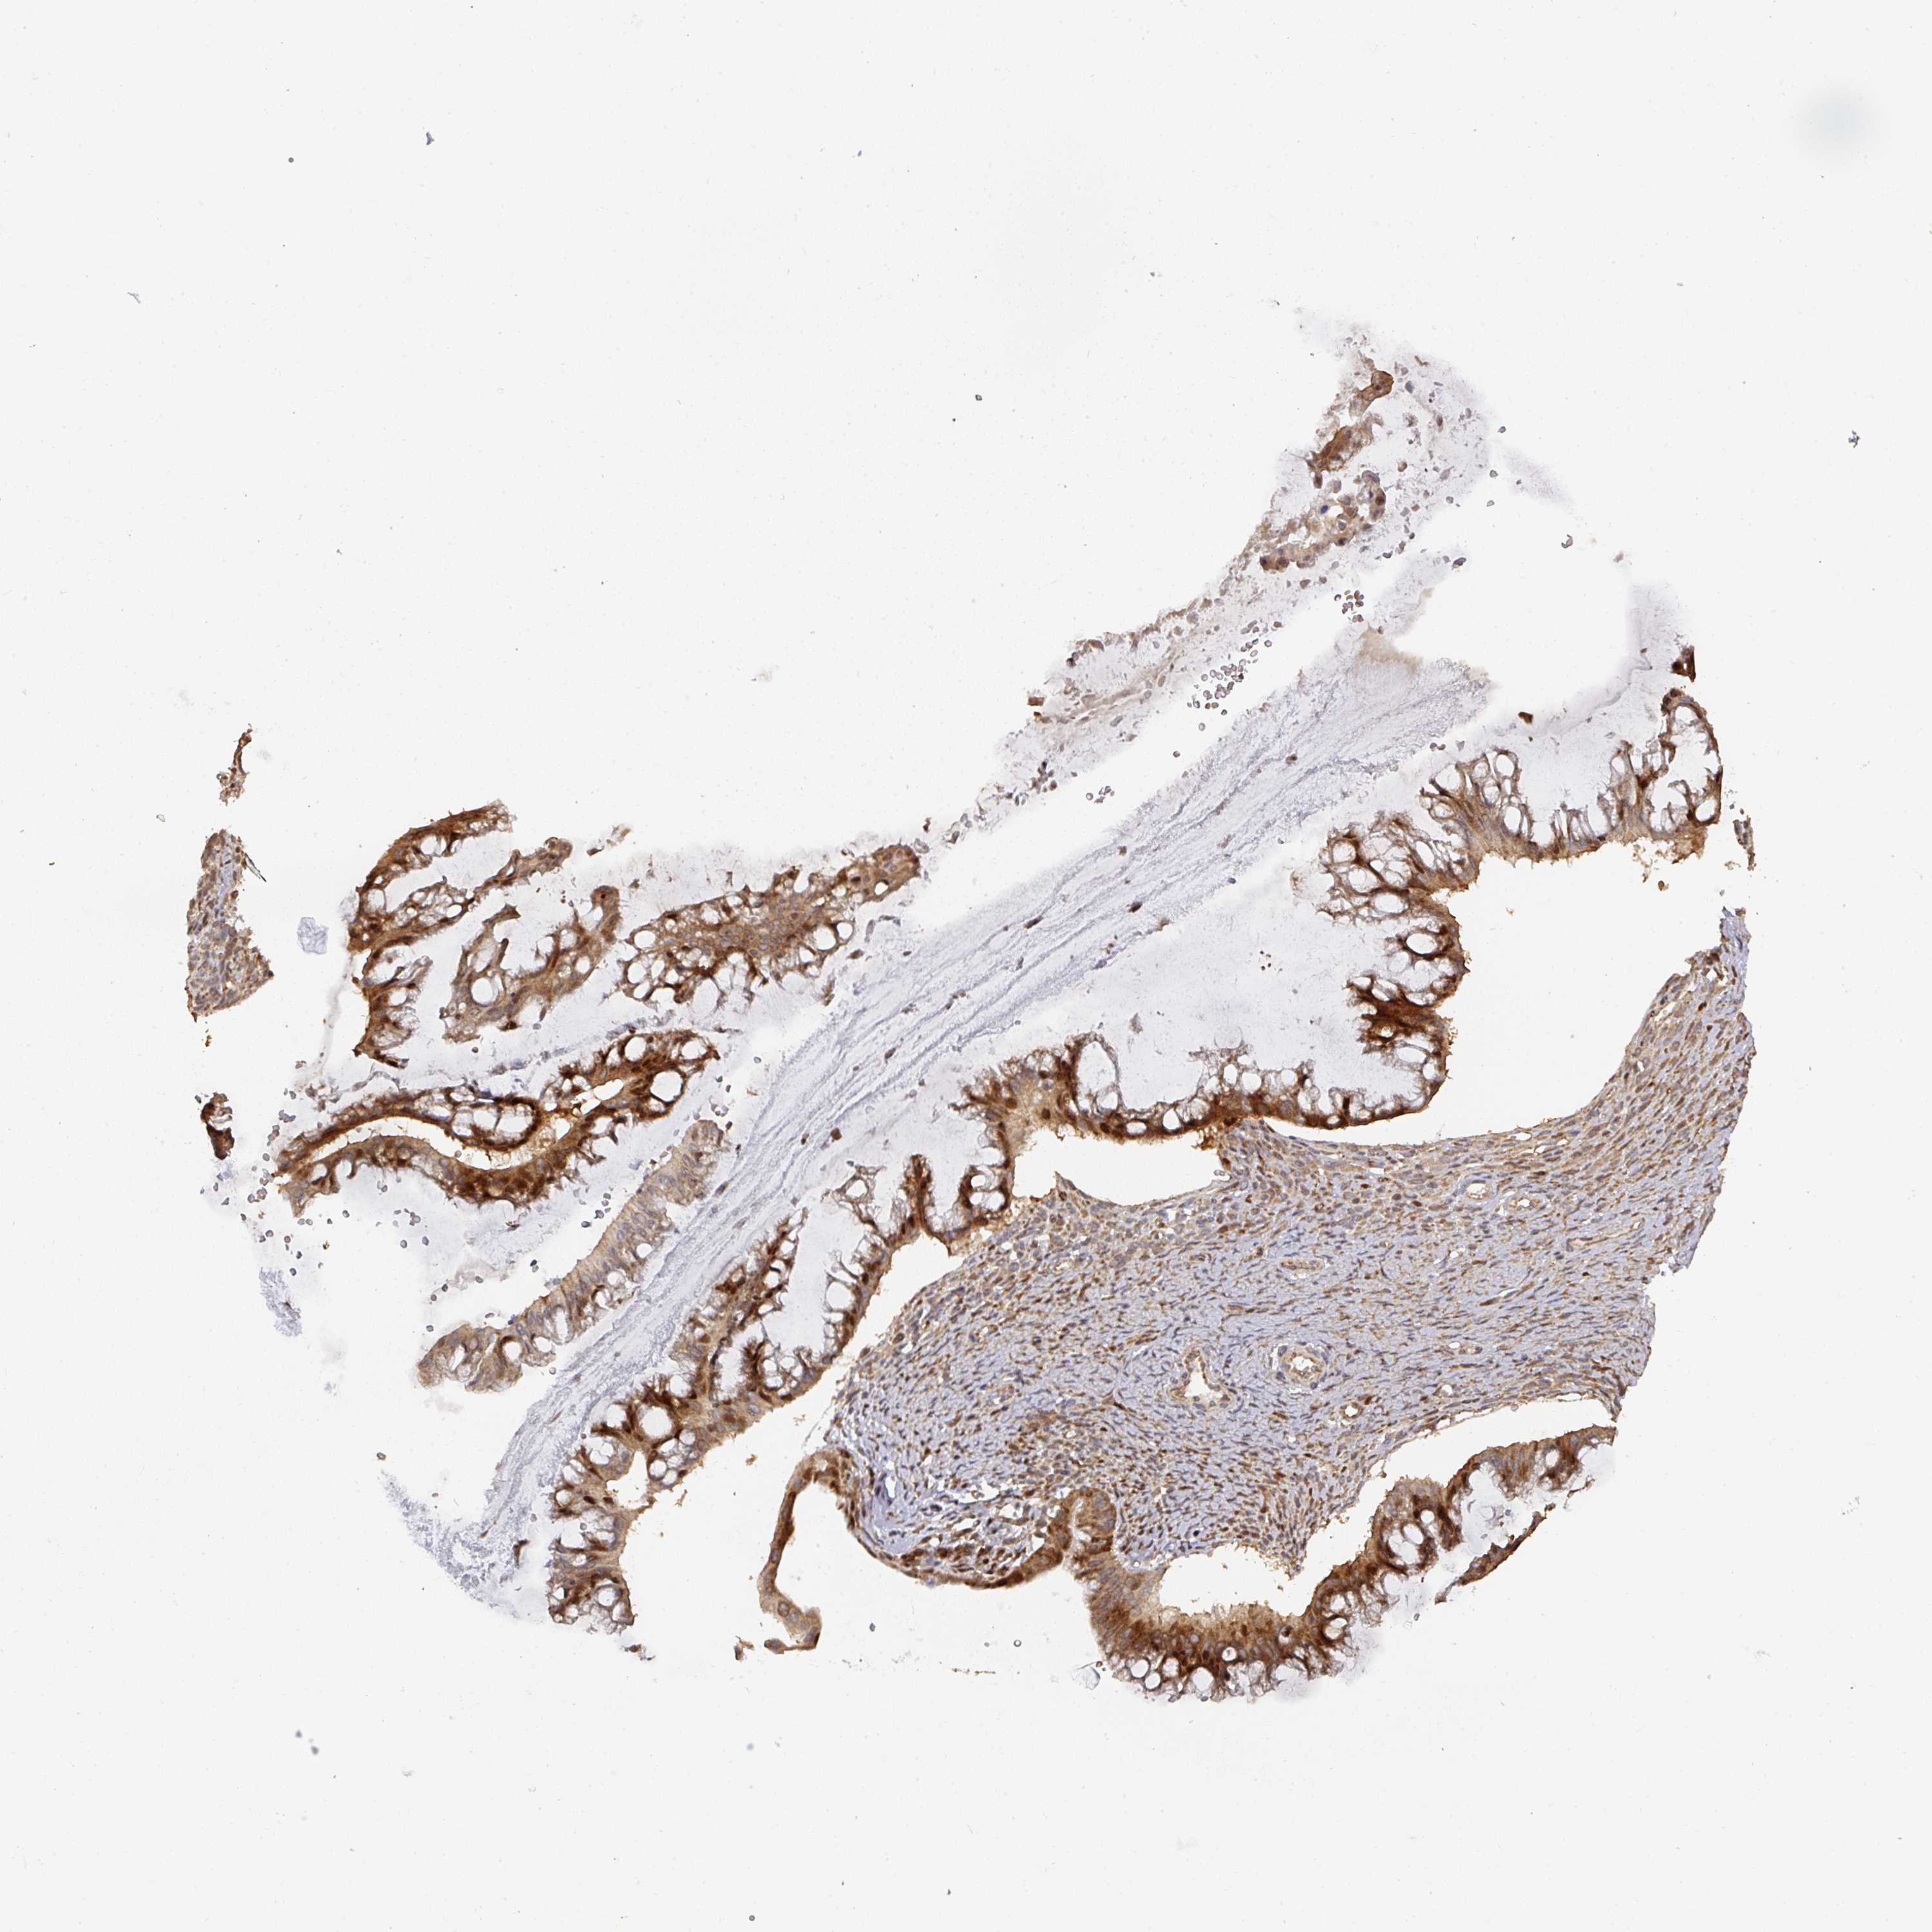

OVARIAN CANCER - Protein expressioni

A mouse-over function shows sample information and annotation data. Click on an image to view it in a full screen mode. Samples can be filtered based on level of antibody staining by selecting one or several of the following categories: high, medium, low and not detected. The assay and annotation is described here.

Note that samples used for immunohistochemistry by the Human Protein Atlas do not correspond to samples in the TCGA dataset.

Antibody stainingi

Antibody staining in the annotated cell types in the current human tissue is reported as not detected, low, medium, or high, based on conventional immunohistochemistry profiling in selected tissues. This score is based on the combination of the staining intensity and fraction of stained cells.

Each image is clickable and will lead to virtual microscopy that enables deeper exploration of all samples and also displays staining intensity scores, fraction scores and subcellular localization as well as patient and tissue information for each sample.

Antibody HPA047237

Staining

High

Medium

Low

Not detected

Intensity

Strong

Moderate

Weak

Negative

Quantity

>75%

75%-25%

<25%

None

Location

Nuclear

Cytoplasmic/membranous

Cytoplasmic/membranous,nuclear

Cystadenocarcinoma, serous, NOS

Carcinoma, endometroid

Cystadenocarcinoma, mucinous, NOS

Carcinoma, NOS